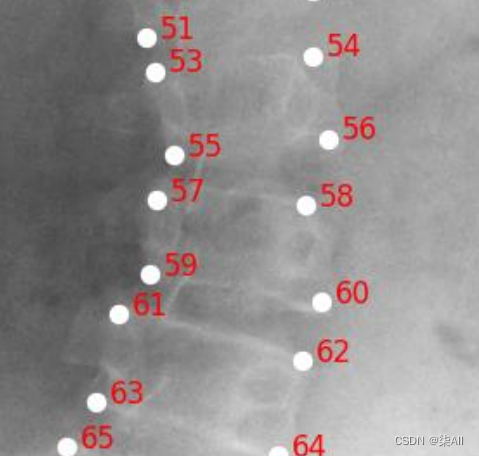

- (6)你看这种58这种点,咱们可以往外标一点,或者把60缩一些

(6)你看这种58这种点,咱们可以往外标一点,或者把60缩一些